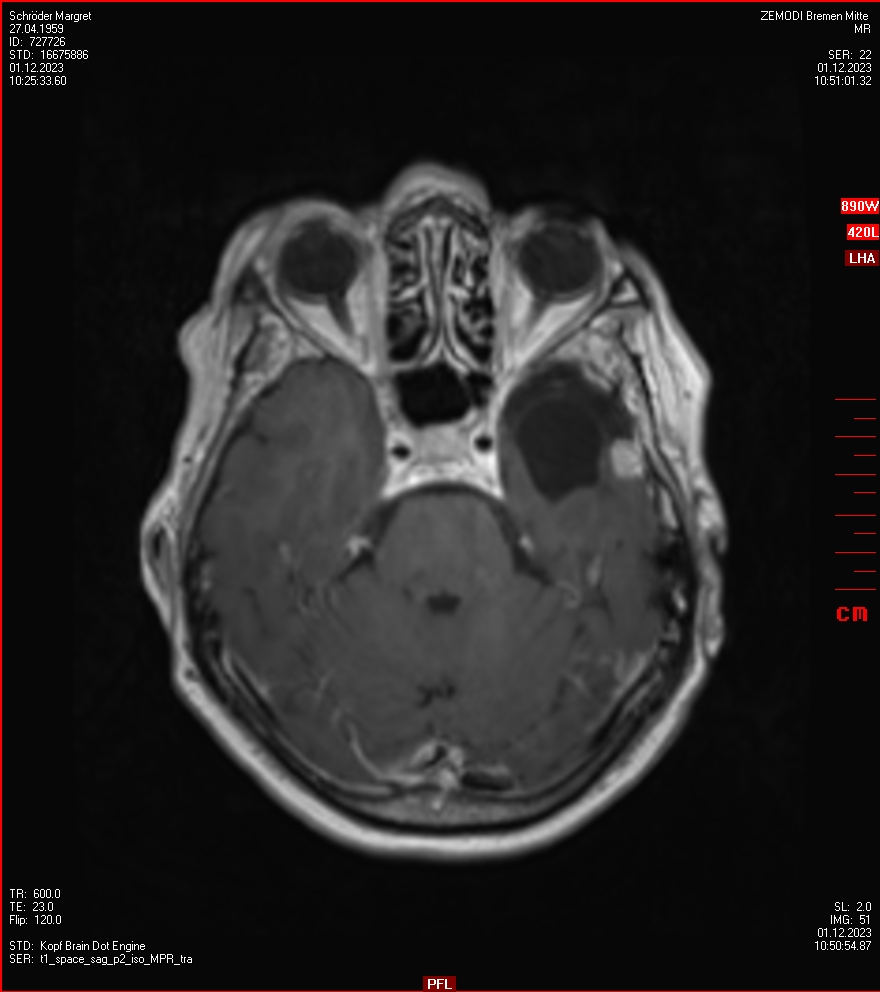

Die letzten drei Bilder Zeigen aus meiner Sicht den Tumor, der im Jahr 2021 bestrahlt wurde.

Zum Vergleich nun auch die Bilder vom 1.12.2023:

Ich denke, in den letzen 12 Monaten sind da ein paar Rezidive gewachsen,  vor 12 Monaten waren sie auch schon zu erkennen - vorher noch nicht. Nun hoffe ich auf den Rat des Spezialisten. Hoffendlich kann man etwas machen.